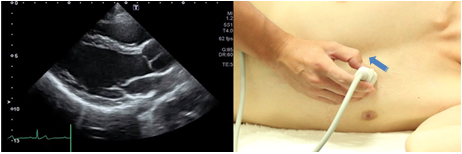

Longitudinal view of the right ventricular outflow tract

To obtain a longitudinal view of the right ventricular outflow tract, rotate the probe slightly in a counterclockwise direction from the position showing the aortic level of the short axis view of the left ventricle and tilt it so that the ultrasound beam is directed slightly outwardly. This view is suitable for the determination of wall motion abnormalities of the right ventricular outflow tract, stenosis of the right ventricular outflow tract, and pulmonary valve stenosis.